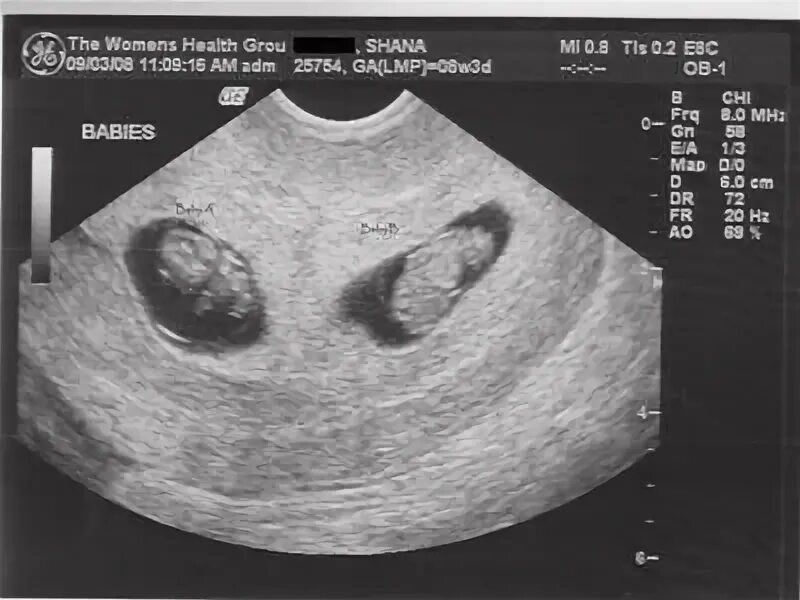

8 недель беременности вторая беременность